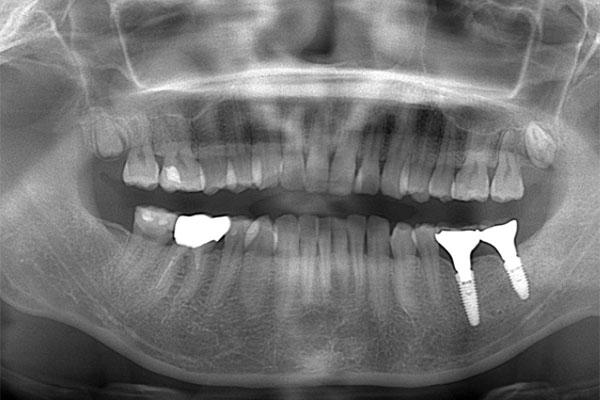

患者様の初診時レントゲン写真

【担当医師所見】

左下奥歯は親知らずが原因でクラウン(かぶせ物)の下まで虫歯になっています。 またその手前の歯は根中央部に大きな透過像(黒い像)が見られます。クラウン除去後、マイクロスコープ下で確認したところ中央部は亀裂が入り保存不可能な状態になっており抜歯となりました。

また右上6番にも大きな透過像があり虫歯となっていることがわかります。

①親知らず手前の歯はクラウン(白い不透過像)直下に大きな透過像(黒い部分)が見られこのような場合は抜歯になる確率が高いです。

②歯根分岐部(中央部)に及ぶ歯周炎ー根尖性歯周炎の原因はクラウン除去後にマイクロスコープ下にて破折線を確認したため抜歯となりました。